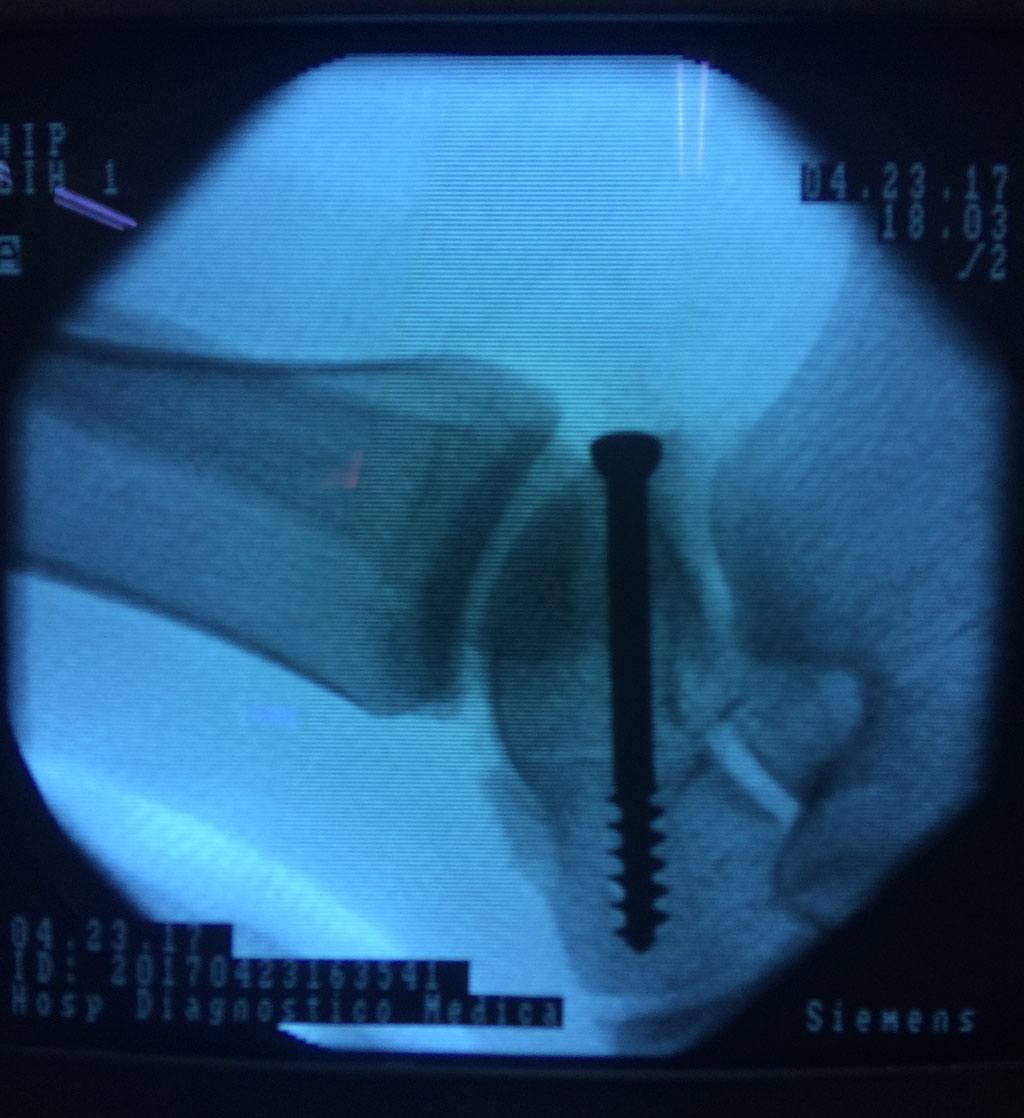

Cuando se necesita cirugía, es probable que esta implique el uso de clavijas de metal, tornillos o placas para sostener los huesos en su lugar mientras la fractura se consolida. Los elementos de soporte pueden ser temporales o permanentes.

Cirugía de Tobi...

Detail Download